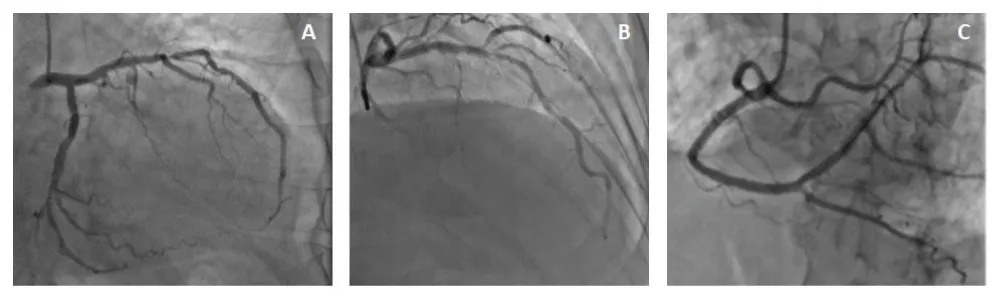

The angiography was performed by 6F right radial access, with Judkins left and right 5F diagnosis catheter. It revealed a tight calcified stenosis of the mid LAD taking the bifurcation with a small diagonal (Figure 1).

Figure 1: Angiographic finding (A: LAD stenosis in caudal view. B: LAD stenosis in cranial view. C: RCA).